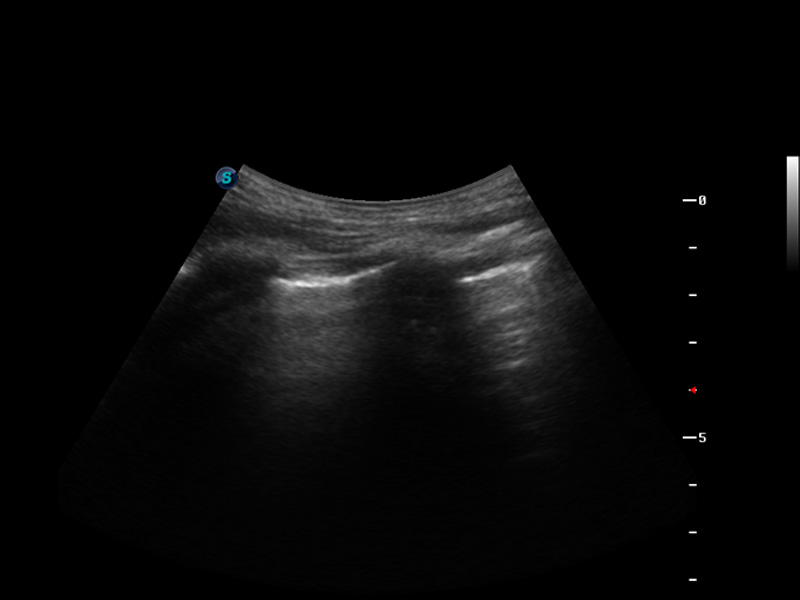

S9便携式彩色多普勒超声诊断仪是milan米兰研发的高端便携彩超设备,外观设计新颖、产品性能卓越。S9在便携超声领域采用了突破传统的触摸屏交互设计,并以先进的软件硬件技术和设计理念,为您带来清晰的图像质量、稳定的工作性能和便捷的操作体验。

μ-Scan微米成像